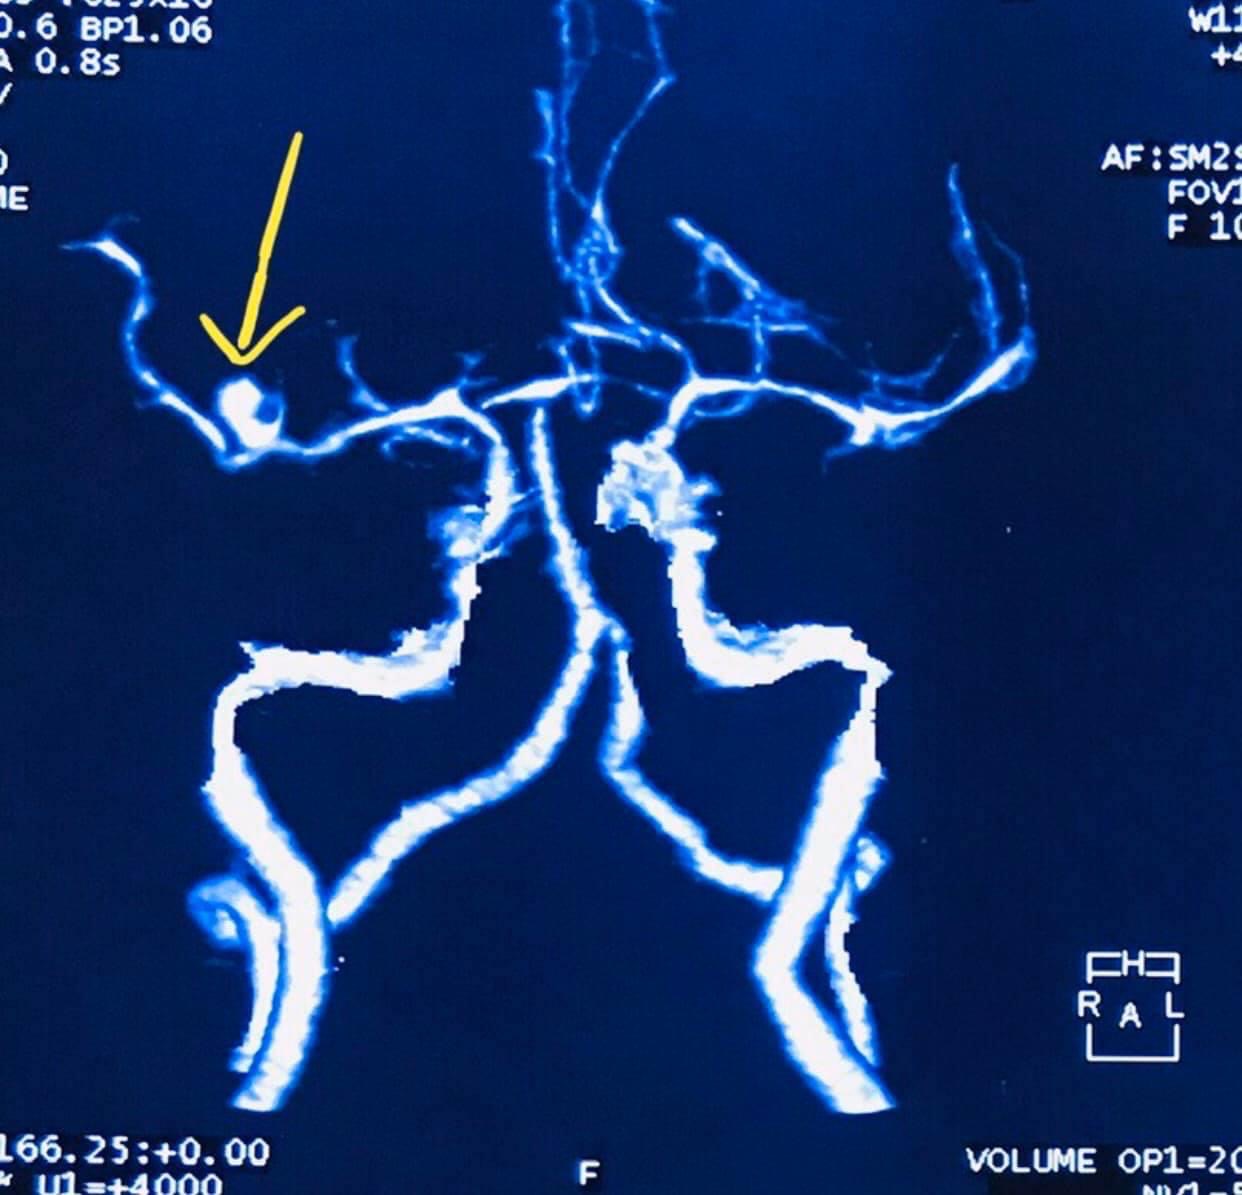

- Clip ligation of brain aneurysms (open microsurgery)